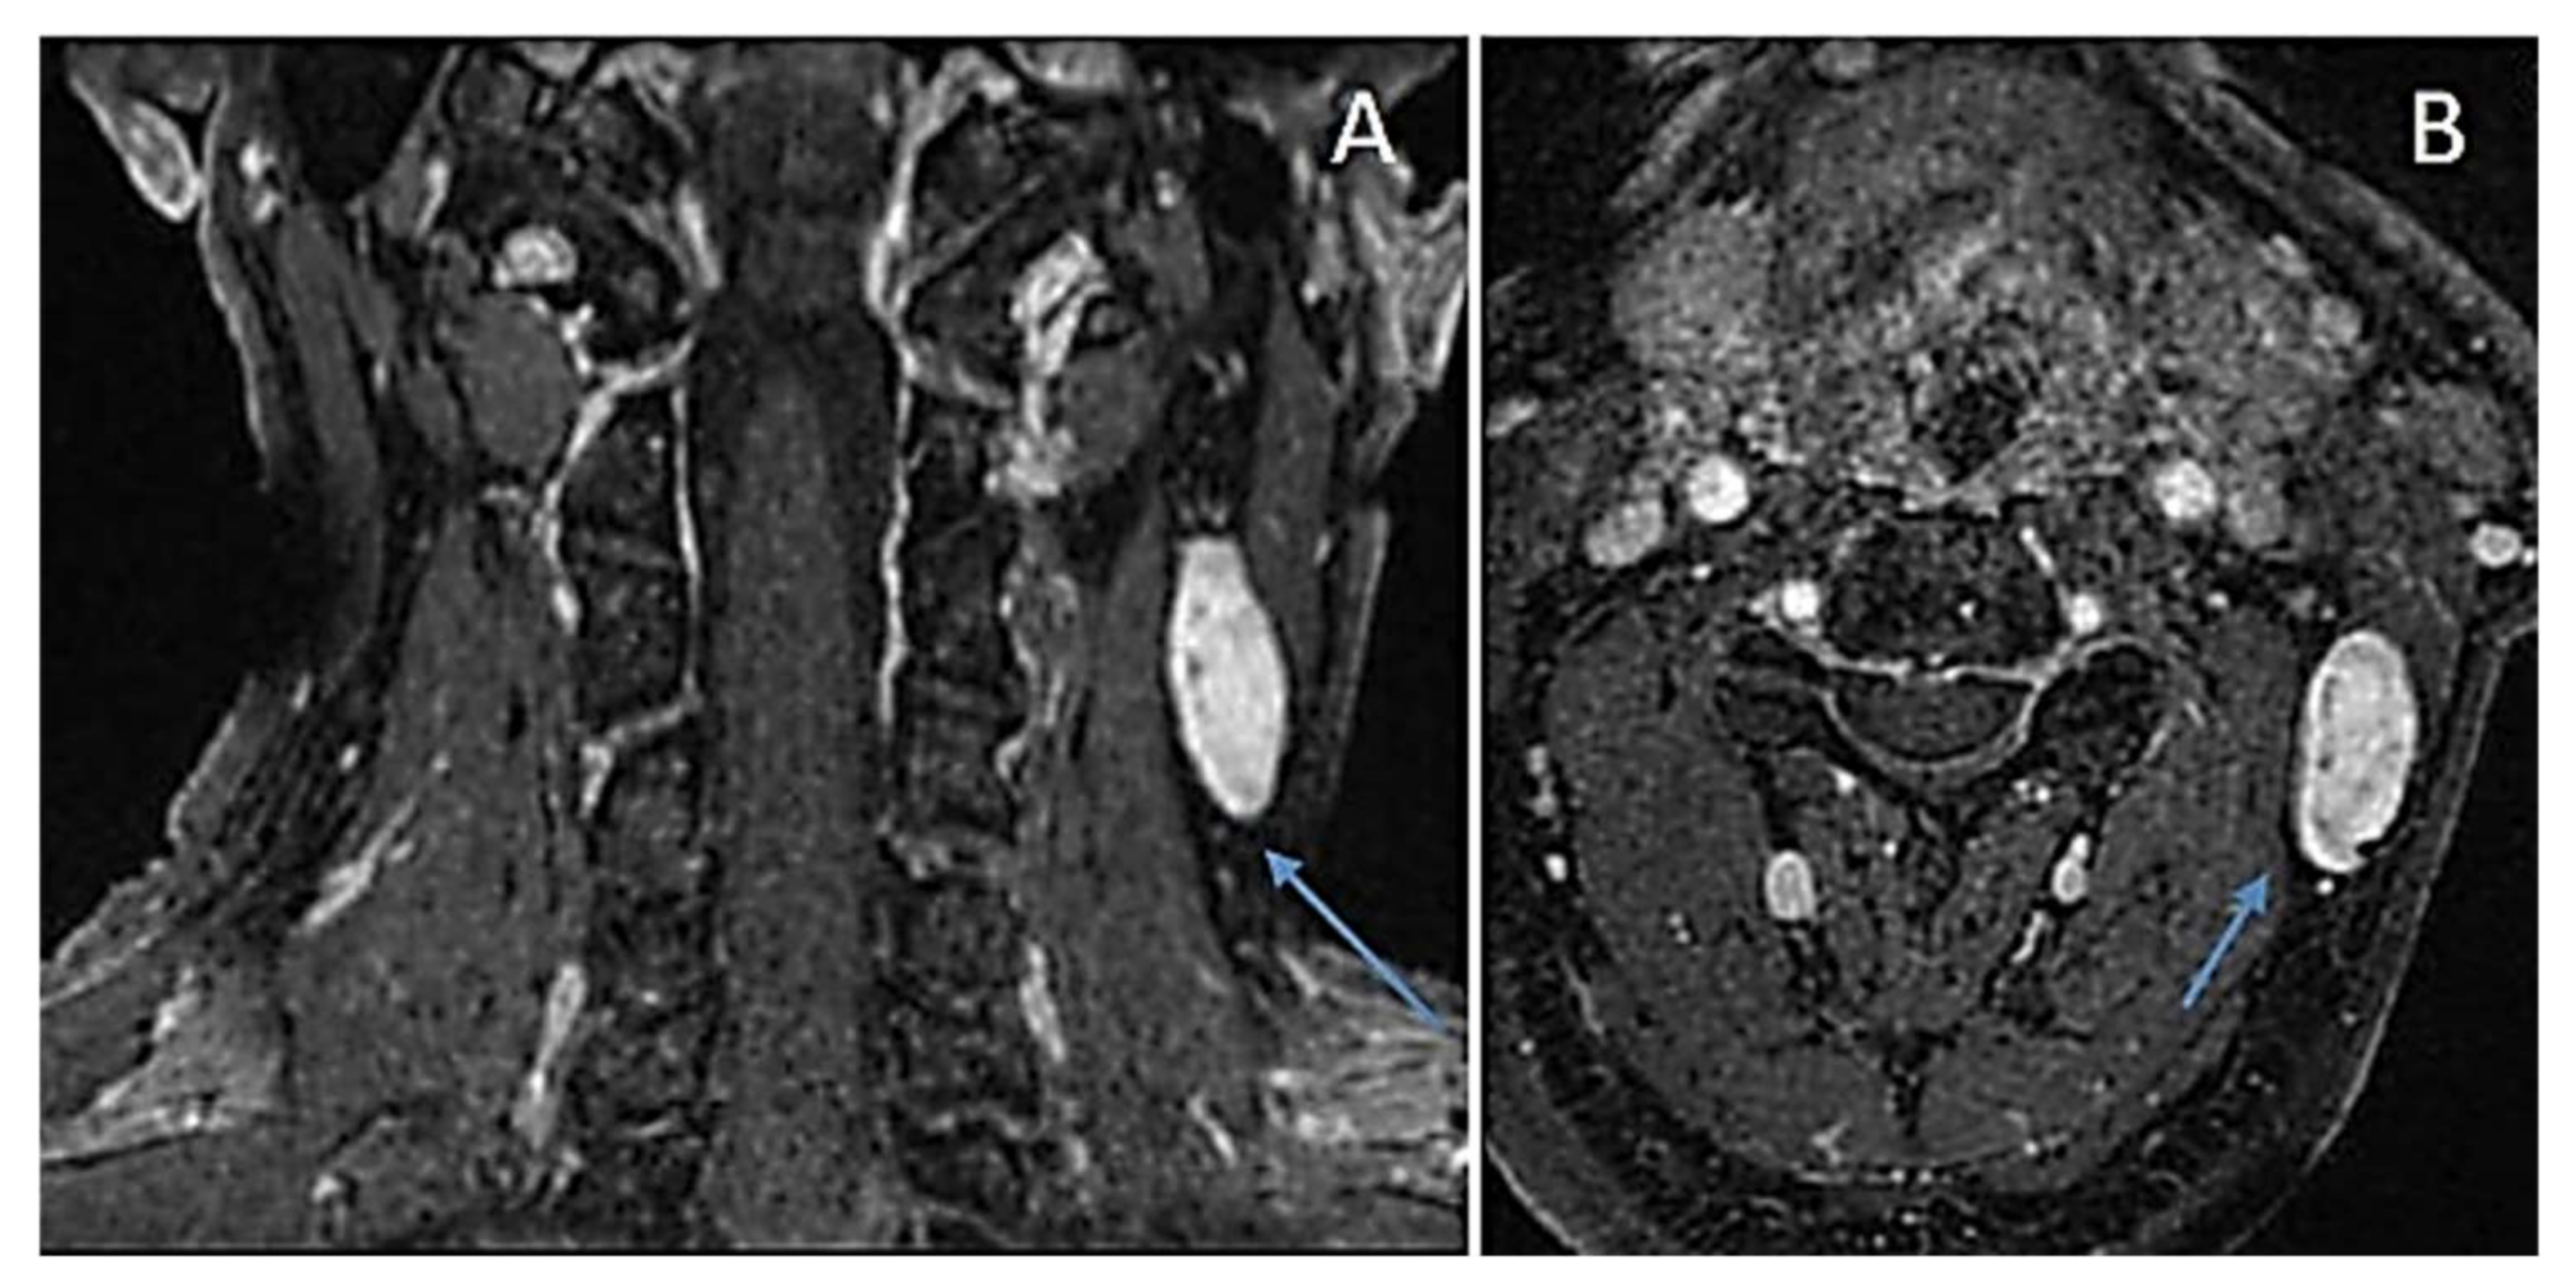

6.4. Plexiform Schwannoma

Immunohistochemical Features